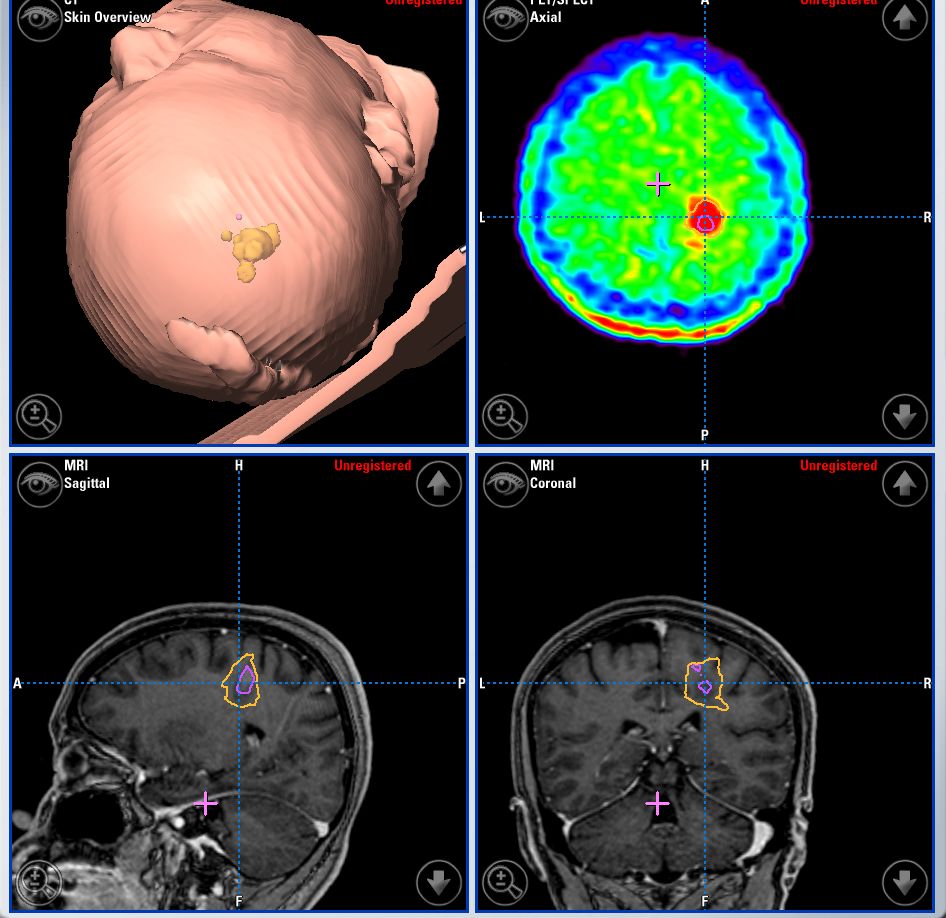

Meningiomas